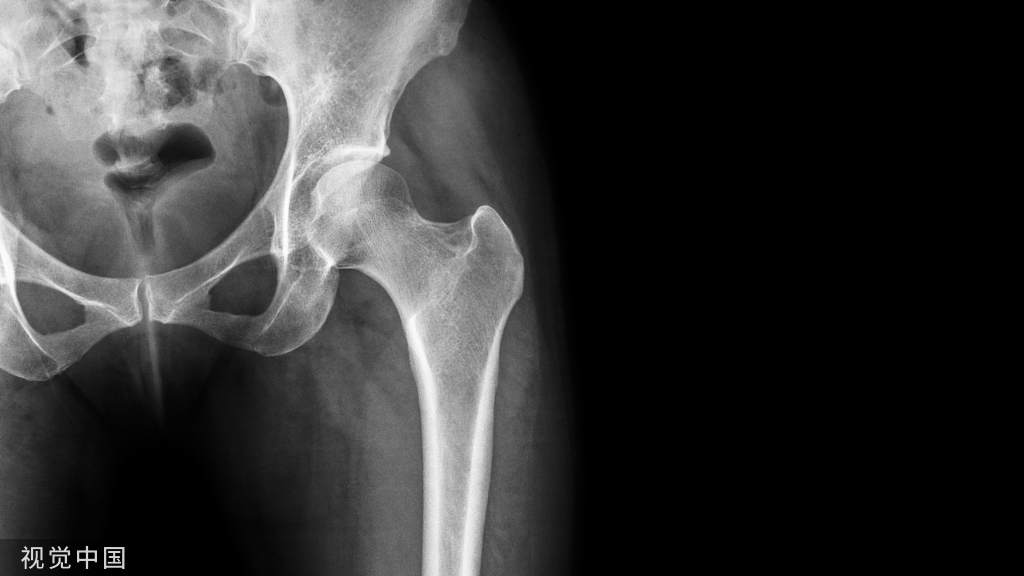

从技术上讲,这些生物力学要求可以通过稳定的假体定位、重建杯外展和前倾、柄前倾、重建髋关节旋转中心、偏移量和腿长来满足(图1),也可以通过使用保留肌肉的外科技术来满足。如果不满足这些生物力学要求,可能会导致机械功能障碍,导致髋关节置换术后不稳定。

图1:全髋关节置换术后的骨盆X光片。为了恢复髋关节运动学,假体定位的特点是牢固的骨支持,重建杯外展(1)和前倾(2),柄前倾和重建髋关节旋转中心,偏移(3)和腿长(4)